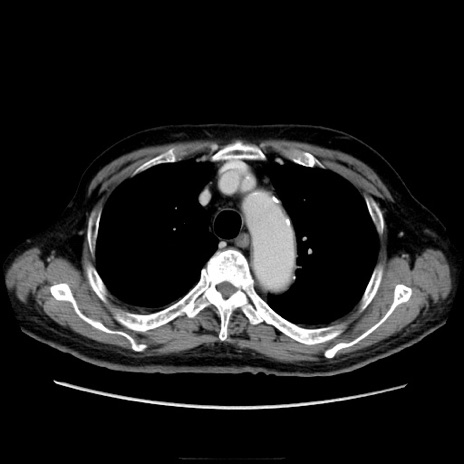

冠状断像

【症例】70歳代男性

【主訴】腹痛

【現病歴】肝硬変・肝細胞癌にてかかりつけの方。約9時間前に食後より腹痛出現。症状が徐々に増悪し、嘔吐出現したため来院。

【既往歴】肝硬変、肝細胞癌(RFA、TACE後)

【身体所見】意識清明、表情苦悶様、BT 36℃、BP 129/78mmHg、P 88bpm、SpO2 97%(RA)、右上腹部から心窩部にかけて圧痛あり、反跳痛なし、筋性防御あり。

【データ】WBC 5800、CRP 0.16